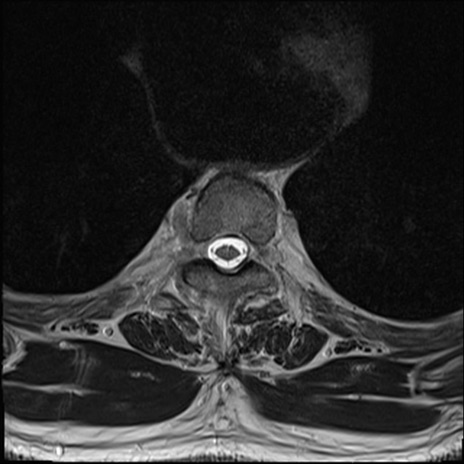

【整形】TIPS症例7 頚椎MRI T2WI(横断像)

頚椎MRI

矢状断像と横断像